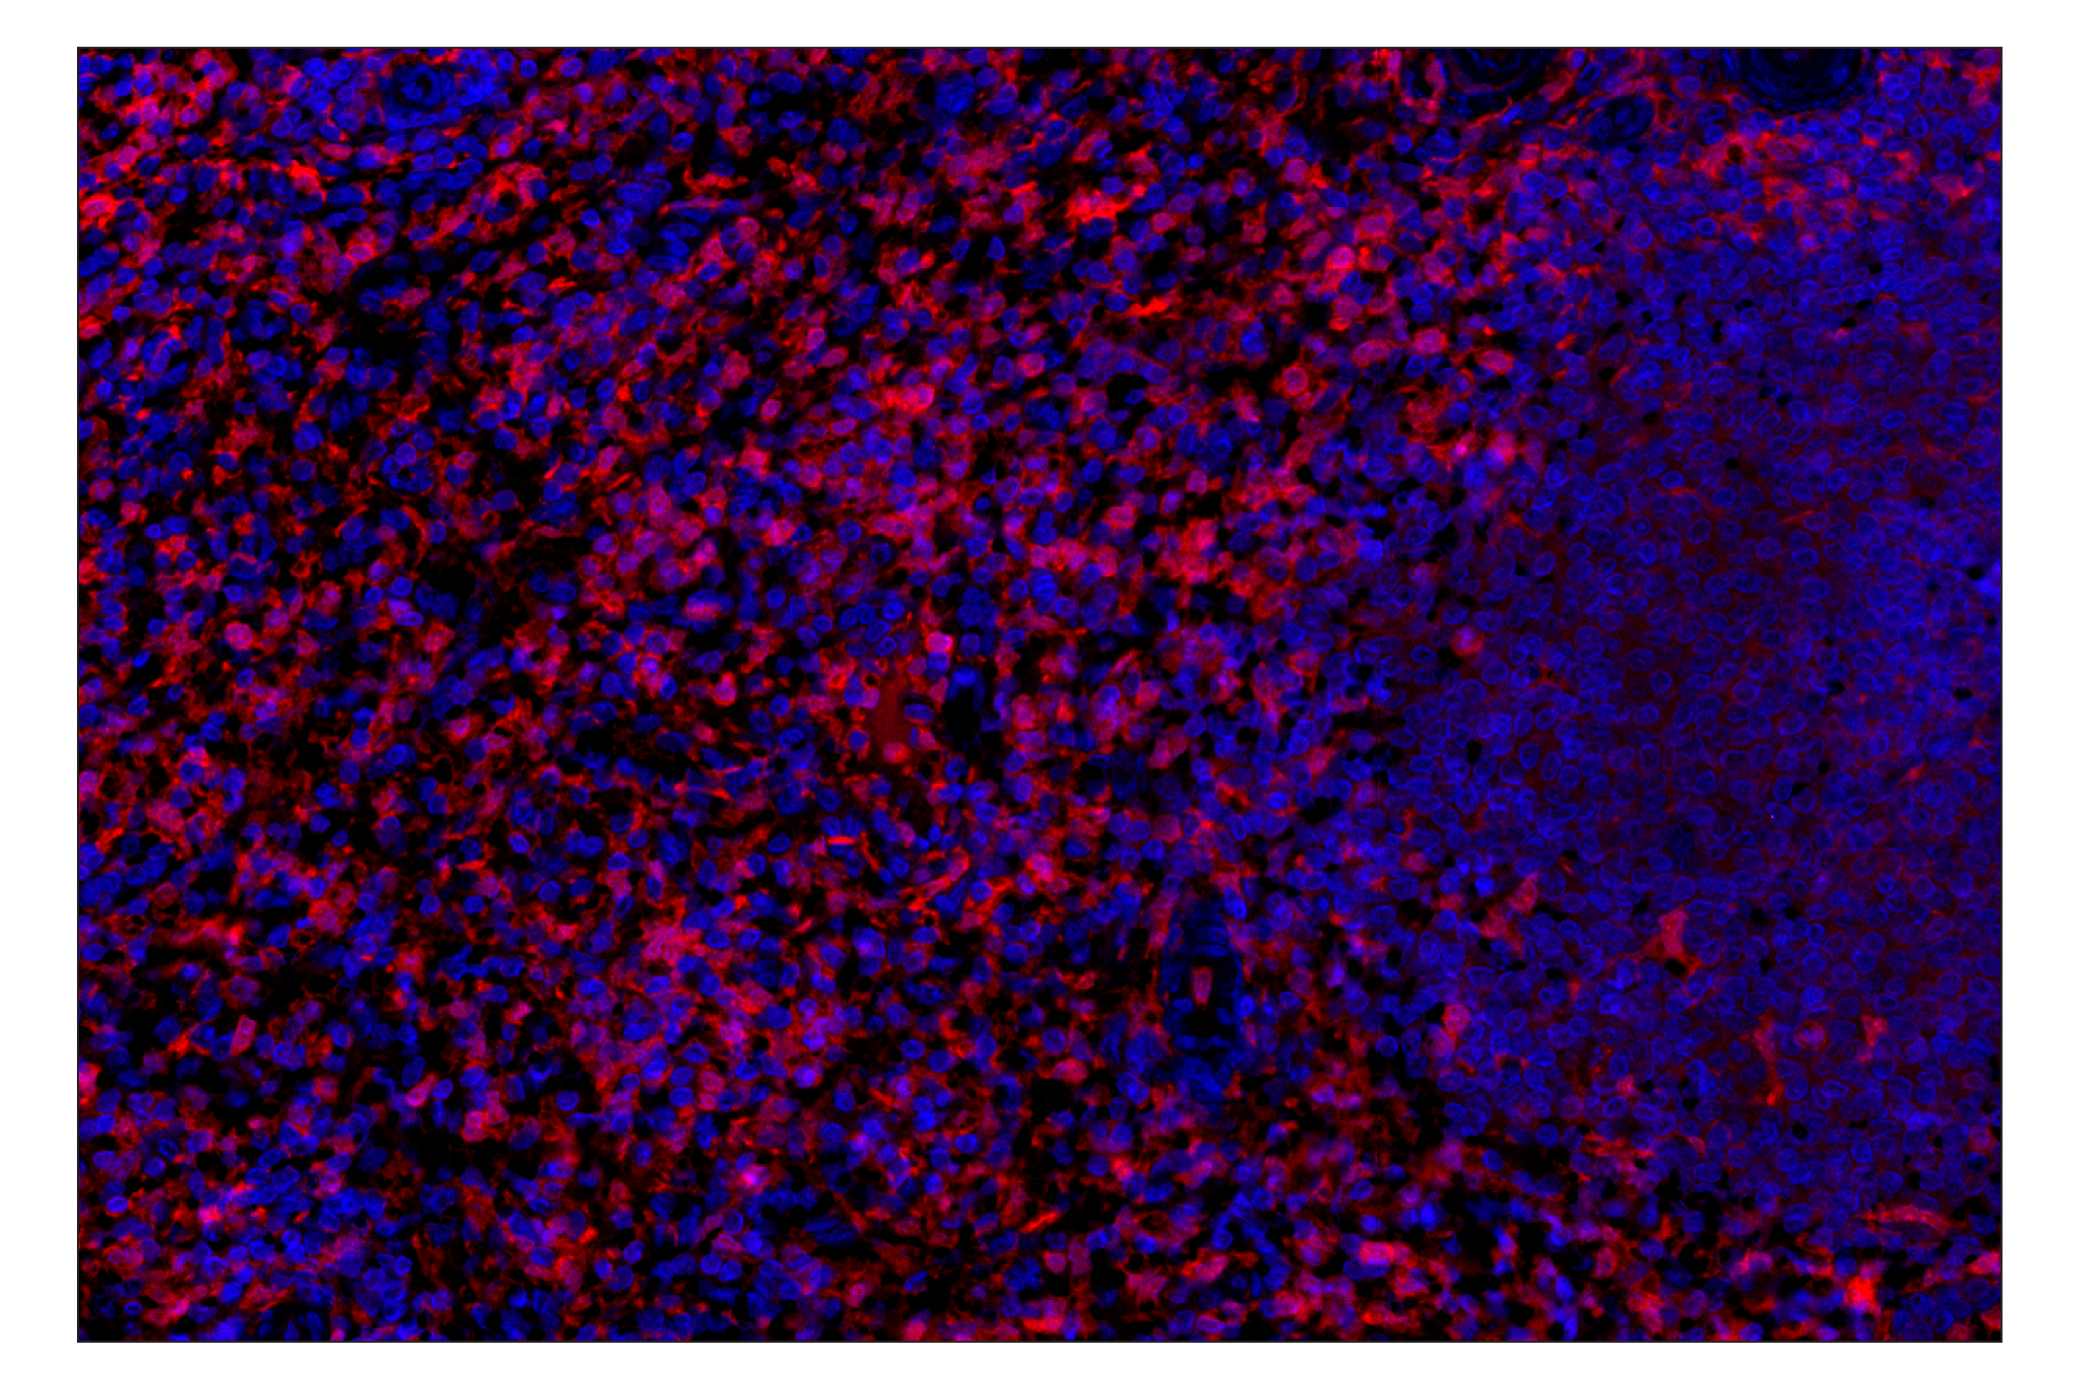

ASC/TMS1 (E1E3I) Rabbit Monoclonal Antibody (Alexa Fluor® 647 Conjugate) #37701

Immunohistochemistry (Paraffin) 1:100 - 1:400

ASC/TMS1 (E1E3I) Rabbit Monoclonal Antibody (Alexa Fluor® 647 Conjugate) recognizes endogenous levels of total ASC/TMS1 protein. This antibody can detect three known isoforms of ASC/TMS1.